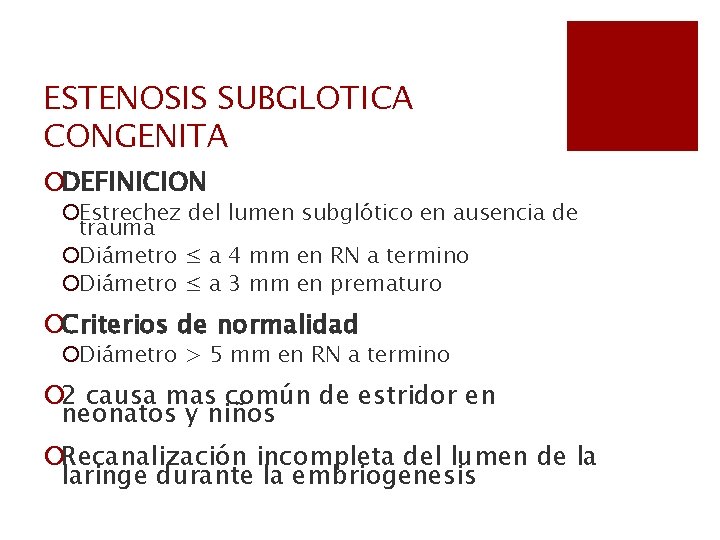

ESTENOSIS SUBGLOTICA CONGENITA ¡DEFINICION ¡Estrechez del lumen subglótico en ausencia de trauma ¡Diámetro ≤ a 4 mm en RN a termino ¡Diámetro ≤ a 3 mm en prematuro ¡Criterios de normalidad ¡Diámetro > 5 mm en RN a termino ¡ 2 causa mas común de estridor en neonatos y niños ¡Recanalización incompleta del lumen de la laringe durante la embriogenesis